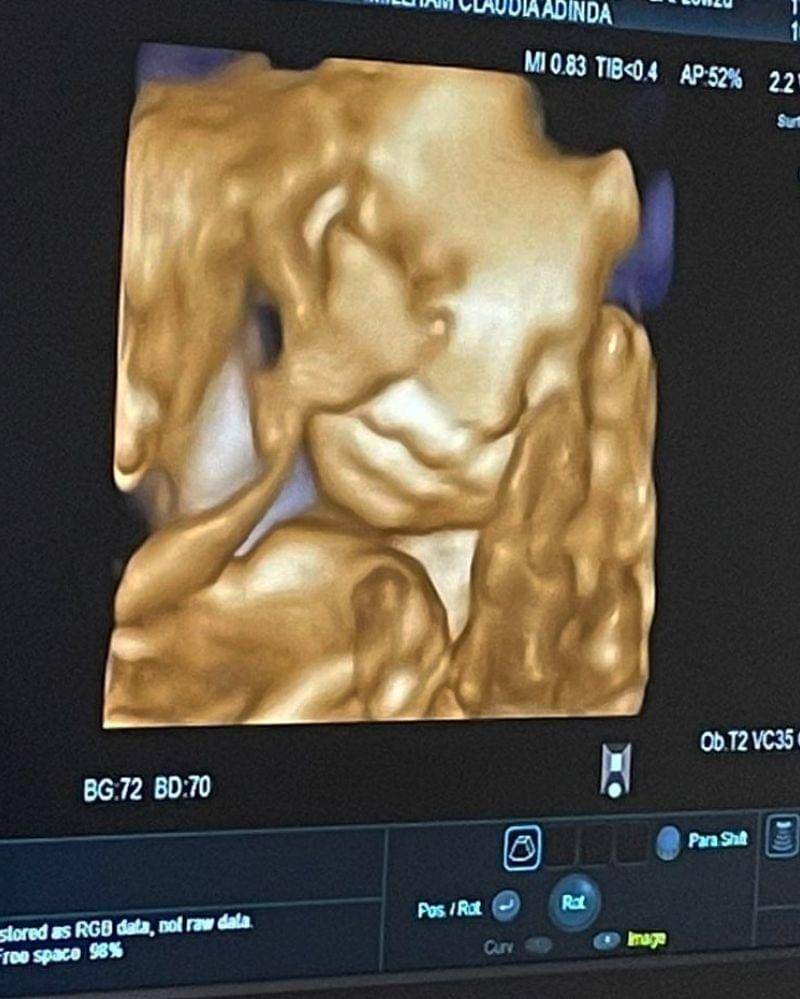

29. Millicent-Mae Bea Nainggolan, anak Claudia Adinda dan Derby Romero

Usai menjalani kehidupan rumah tangga selama empat tahun, akhirnya aktor sekaligus penyanyi Derby Romero resmi berstatus sebagai Papa. Sang istri, Claudia Adinda telah melahirkan anak pertamanya pada 20 Januari 2022 lalu.

Bayinya yang berjenis kelamin perempuan diberi nama Millicent-Mae Bea Nainggolan. Kehadiran Millie Mae pun membawa warna baru di kehidupan Derby dan Claudia.